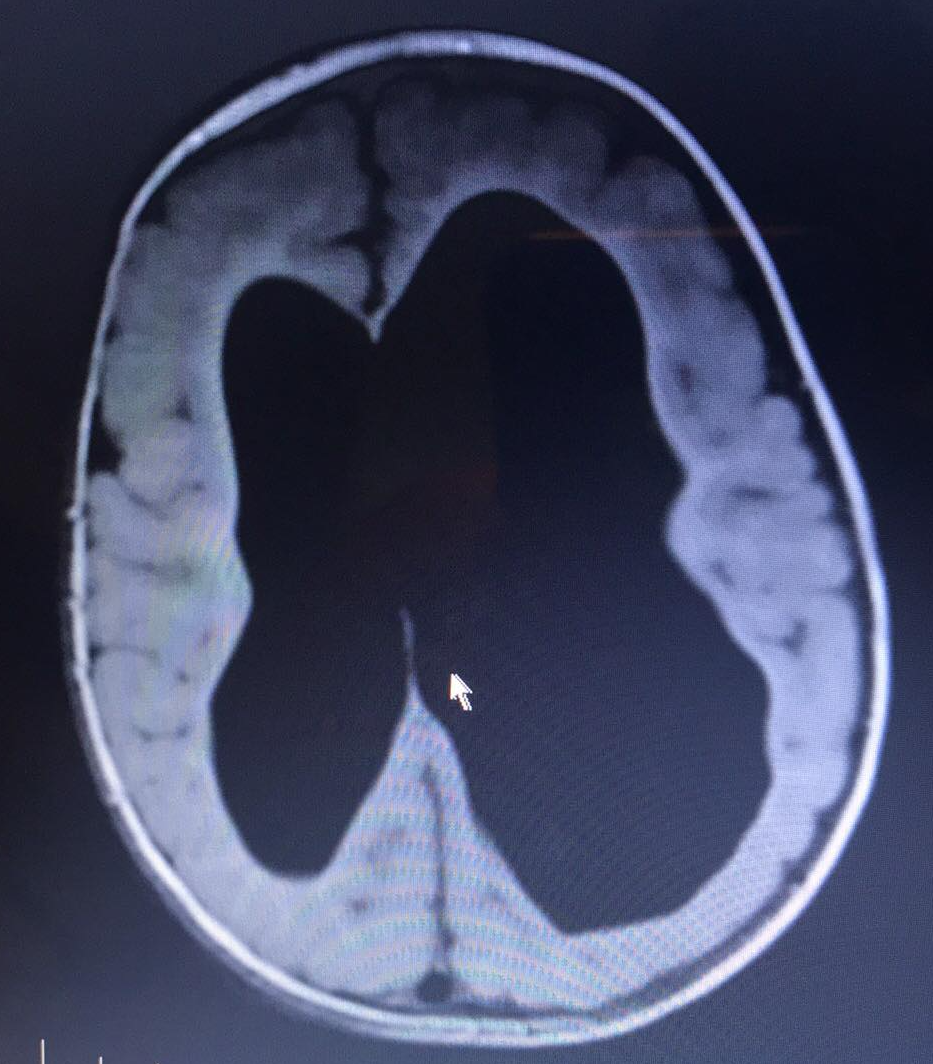

Bilateral Severe Ventriculomegaly